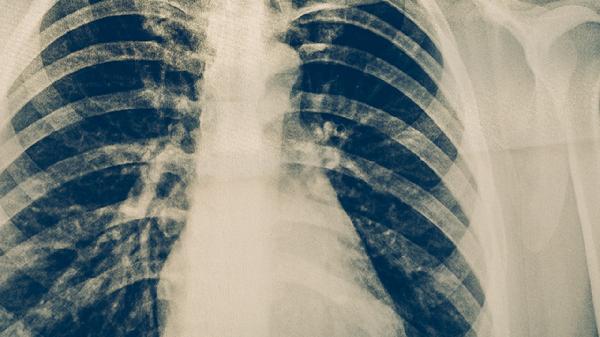

间质性肺炎CT表现

间质性肺炎的CT表现主要有毛玻璃样影、网格状影、实变影、支气管血管束增粗、蜂窝状改变等。